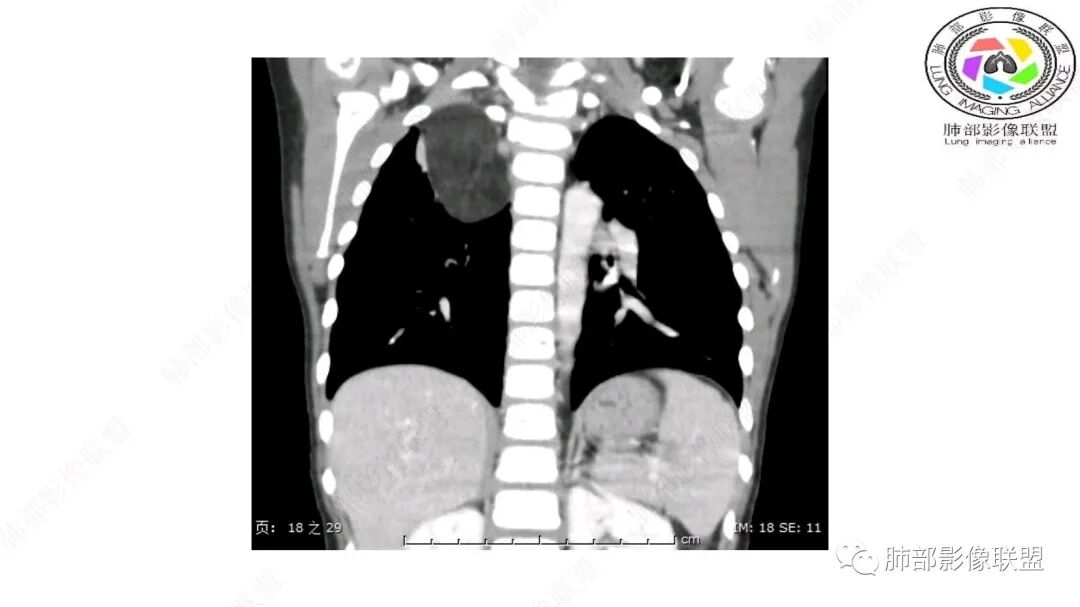

病灶属于交界区,主体位于肺内,占位效应明显,前方突入胸壁,胸腺受压变形,胸膜显示欠清楚;病灶包绕上叶肺动脉;似乎有体动脉供血。符合肺内的点:包绕上叶肺动脉分支;符合纵隔的点:前方似乎突入胸壁,与胸腺关系比较密切,但是与上腔静脉的关系提示病灶不支持纵隔来源,前纵隔的常规会将上腔静脉受压后移、外移,这是不符合的。

1.右上肺-纵隔交界区巨块影,主体位于右肺一侧,紧贴胸腺、头臂干、右锁骨下动脉、上腔静脉、奇静脉等,不能分离,但病灶整体边界清楚。注意上述相邻腔静脉等结构未见受压变形,纵隔亦未见明显向左推移,至少提示两点:

1)病灶相当柔软。

2)位于纵隔内或纵隔胸膜的可能性较小,因为受纵隔胸膜反作用力影响不明显。

2.肺动脉穿行也许是肺内来源最重要支持点!

CT扫描对脂肪类肿瘤常有独到价值。肿块孤立、边界清楚,未见周围浸润,较均匀脂肪样低密度,高度提示为良性!

脂肪母细胞瘤由成熟程度不同的脂肪组织、纤维间隔、黏液基质、小血管丛等间质成分组成,以脂肪组织与黏液样基质为主,其影像学表现取决于上述组织成分。典型的CT和MRI表现为:前后纵隔均可发生,常见于前纵隔;肿块大小不一,直径多在3cm~7cm,密度均匀,CT值呈水样或脂肪密度,脂肪组织密度或信号为主的肿块,其内密度或信号不均匀,可见粗细不一的分隔影,且有结节、片状影,后者可呈轻中度强化;结节状肿瘤包膜完整;弥漫性者包膜不明显,常呈浸润性生长;周围结构为受压和推移改变,可有少量胸腔积液,淋巴结无增大。